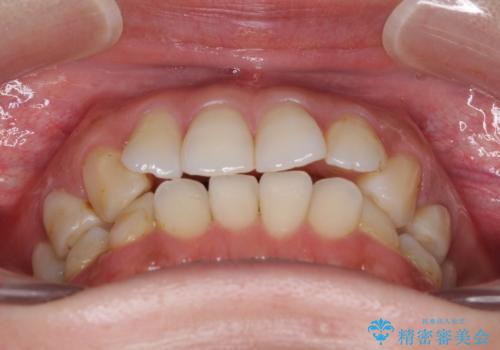

- 失活により変色した歯と不揃いな口元を気にして来院された患者様です。

口元をインビザラインにより歯列を整え、その後に失活している奥歯をオールセラミッククラウンにて補綴治療することとしました。

長時間のマウスピース装着と、患者様自身でのゴムかけに協力いただき、自然な口元に仕上げることができました。

気になっていた変色した歯もオールセラミッククラウンで本物の歯のようになり、患者様には大変満足していただきました。